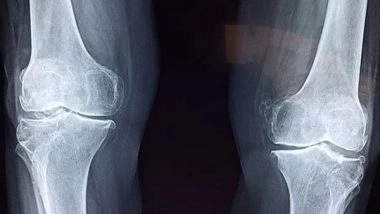

The skeleton is a highly dynamic structure that changes shape and composition throughout a person's life. Osteocytes are the most abundant cell type in bone but have proved difficult to study because they are embedded within the hard mineral structure of the skeleton.

Inside the bone, osteocytes form a network similar in scale and complexity to the neurons in the brain (with over 23 trillion connections between 42 billion osteocytes) that monitors bone health and responds to ageing and damage by signalling other cells to build more bone or break down old bone. Diseases such as osteoporosis and rare genetic skeletal disorders arise from an imbalance in these processes.